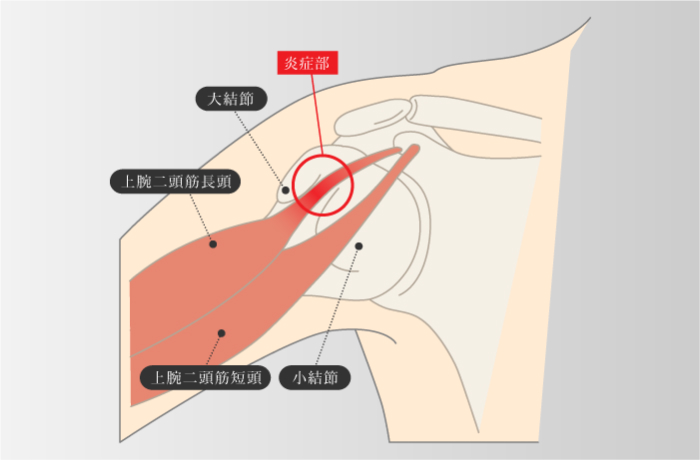

上腕二頭筋長頭腱炎

-

上腕二頭筋長頭腱が結節間溝を通過する場所で炎症が生じ、それが肩の痛み症状として発症することがある。主な原因は、腕を肩の上にあげる動作を繰り返して行うことによる上腕二頭筋の過剰使用